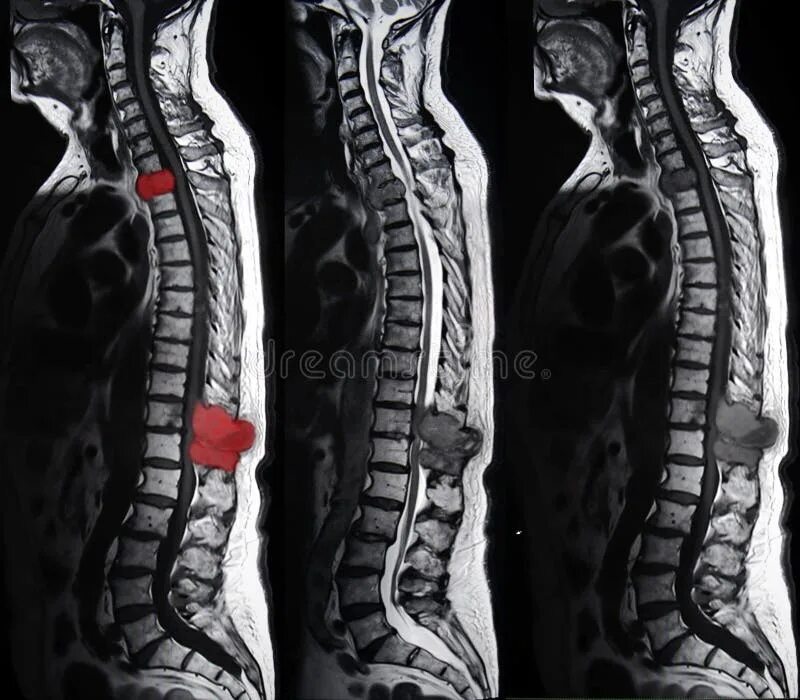

4 стадия метастазы позвоночника